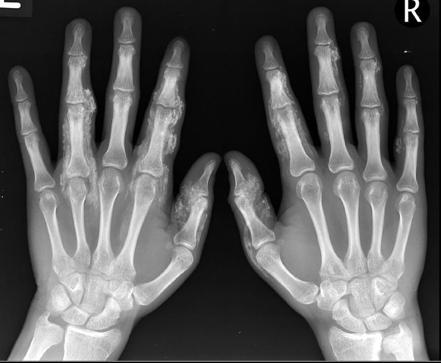

deforming non-erosive arthropathy characterized by ulnar deviation of the second to fifth fingers with metacarpophalangeal joint subluxation.

Jaccoud arthropathy

Reducible subluxations of the MCPs and PIPs

MCP subluxation with ulnar deviation. No erosions. Related to ligamentous laxity

Jaccoud arthropathy (think SLE)

historically described as being secondary to recurrent rheumatic fever (now associated with SLE) deforming non-erosive arthropathy characterized by ulnar deviation of the second to fifth fingers with metacarpophalangeal joint subluxation.